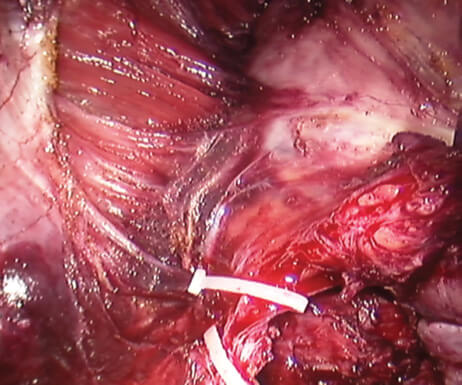

Στον καρκίνο του προστάτη, η χρήση διεγχειρητικά του ρομποτικού υπερήχου προσφέρει πολλά και σημαντικά πλεονεκτήματα. Η αναγνώριση και διατήρηση των αγγειονευρωδών δεματίων που είναι υπεύθυνα για τη διατήρηση της εγκράτειας και της στυτικής λειτουργίας καθίσταται ευκολότερη και τα ποσοστά της είναι μεγαλύτερα λόγω της συνδυασμένης χρήσης ρομποτικής χειρουργικής και υπερήχου. Έτσι παρέχεται μεγαλύτερη ακρίβεια στην παρασκευή των ιστών, καλύτερη αναγνώριση των αγγείων που αιματώνουν τον προστάτη, μεγαλύτερη ευκρίνεια στην αναγνώριση των ανατομικών ορίων του αδένα, καλύτερα ποσοστά αρνητικών χειρουργικών ορίων μετά την επέμβαση. Πρώιμες μελέτες της χρήσης των υπερήχων στη ρομποτική ριζική προστατεκτομή που έγιναν στις ΗΠΑ εμφανίζουν ποσοστά μέχρι 95% στη διατήρηση της εγκράτειας και της στυτικής λειτουργίας, καθώς και στην επίτευξη αρνητικών χειρουργικών ορίων.